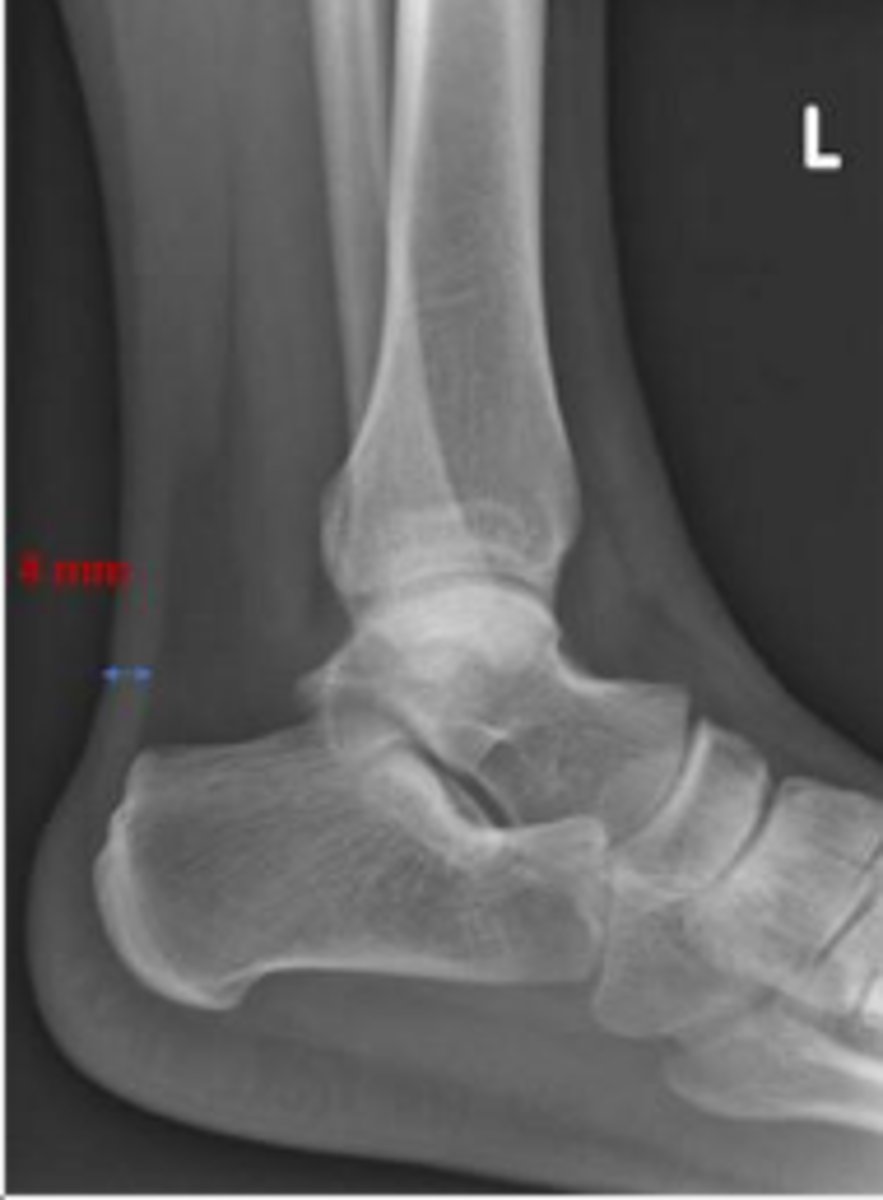

Heel pad measurement

What is the name of the assessment?

Females: average 19mm (maximum of 23mm)

Males: average 19mm (maximum of 25mm)

What is the normal range for the assessment?

Achille's tendon thickness

4-8mm

Yes

Is the assessment within normal limits?

Overuse, ill-fitting shoes, tendinosis/tendinitis,

rheumatological diseases, etc.,

Name 2 conditions that may result in an increase in the measurement beyond the upper limit of normal ?